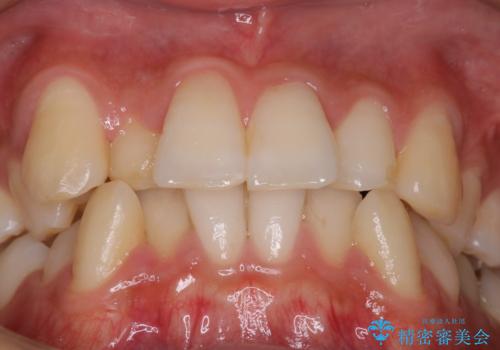

前歯のガタガタを治したい。

- 凸凹を治したいと来院された患者様です。

インビザラインにて、遠心移動を行いながら綺麗に配列することができました。

側切歯が低位の場合、反対咬合を改善した後に挺出させるのはワイヤーの方が適しています。